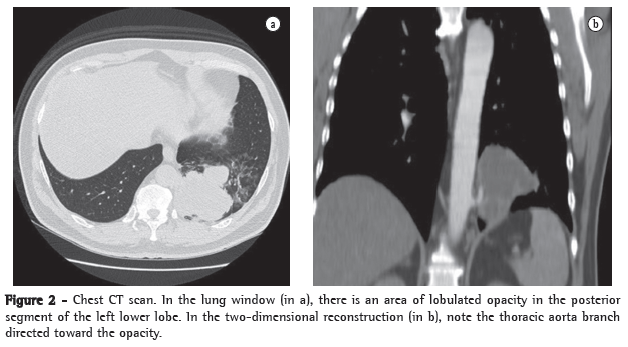

Physical examination revealed good general health, no fever, an HR of 88 bpm and an arterial pressure of 90-145 mmHg. The cardiac auscultation was normal, and examination of the lung revealed reduced expansion and diminished breath sounds in the lower third of the left hemithorax, as well as dullness to percussion in this same region. The rest of the physical examination revealed no abnormalities. The results of the laboratory tests performed at admission, such as blood workup, lipid profile, coagulation profile, determination of electrolyte concentrations, renal function test and hepatic function test, were normal. The ESR was 32 mm/h. Serology for HIV was negative. A chest X-ray at admission revealed opacity in the posterior segment of the left lower lobe (Figure 1). A CT scan of the chest with two-dimensional reconstruction revealed an aortic branch directed toward the pulmonary opacity (Figure 2), which is consistent with a diagnosis of pulmonary sequestration. The patient was referred for surgery, and a left lower lobectomy was performed to resect the anomalous pulmonary tissue (Figure 3). After the macroscopic analysis of the surgical sample, the patient was diagnosed with intralobar sequestration. The postoperative evolution was favorable, and the patient was discharged to outpatient treatment.

In the investigation of a suspected case of pulmonary sequestration, imaging studies have two principal objectives: to rule out other pathologies; and to confirm the presence of an anomalous arterial supply.(12-15) The most common radiological presentation is a homogeneous opacity in the posterior basal segment of the left lower lobe. Arteriography allows the characterization of anomalous arteries, providing valuable information for preoperative planning.(13) Similarly to nuclear magnetic resonance imaging, spiral CT allows the visualization of the source and course of the vessels in most cases. In such cases, angiography is unnecessary.(10,15) The diagnosis of pulmonary sequestration is confirmed by multichannel CT scans of the chest with intravenous contrast and reconstruction, there being no need for aortography or magnetic resonance imaging of the chest and abdomen, since CT scans of the chest and upper abdomen allows the visualization of the arterial vessel communicating with the sequestration and of the changes in the lung parenchyma.(14,15)